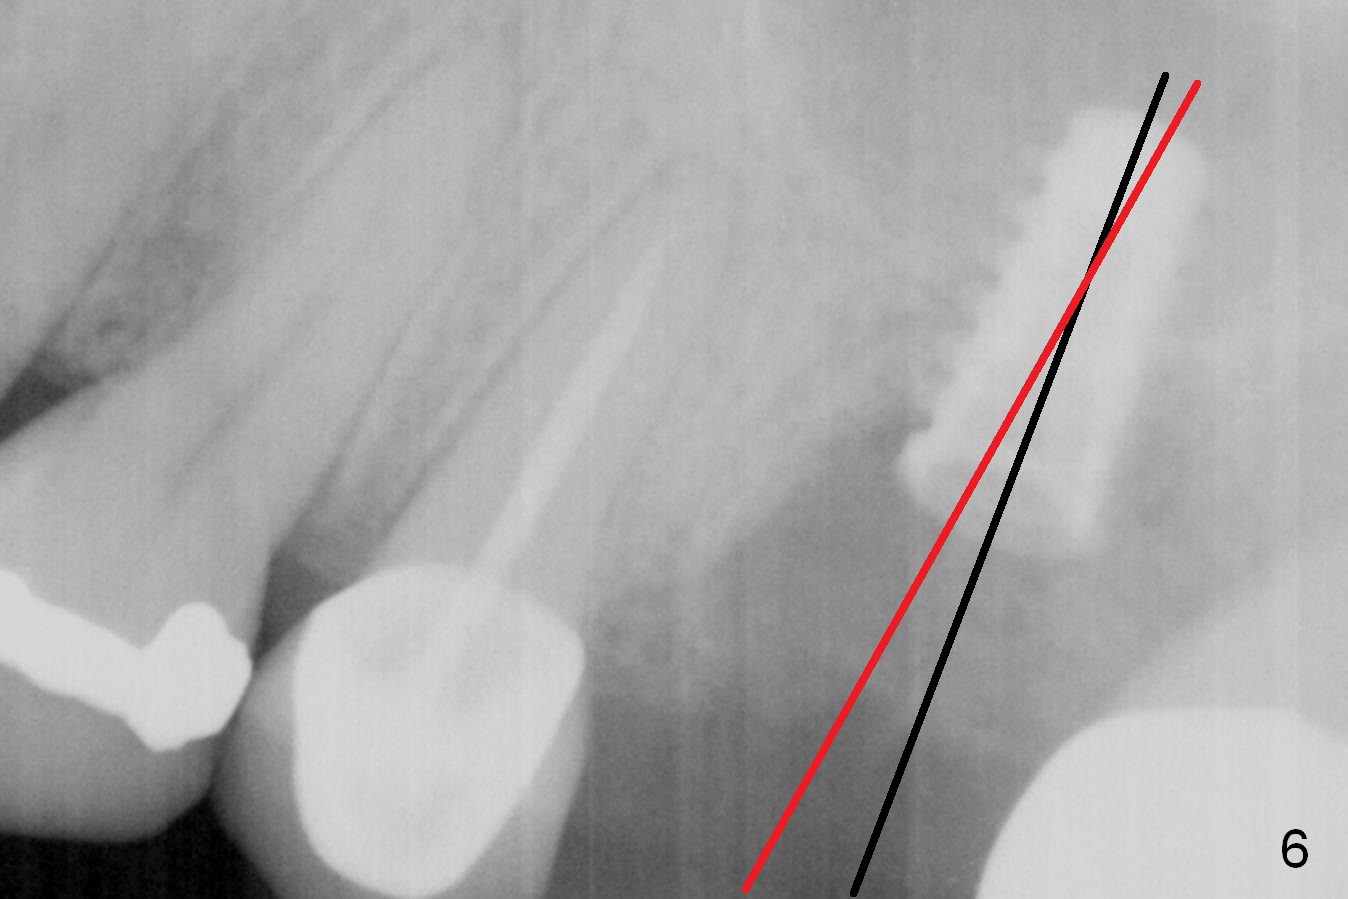

When the affected tooth is extracted, the suitable site for implantation is the large palatal socket. Osteotomy is initiated with Magic Expander 3.0 mm (red circle or arrow in Fig.1 (occlusal view), 2 ((coronal section)) as buccally as possible, since the palatal plate (P) is shorter than the buccal one (B in Fig.2). The sinus floor turns out to be thin. When the osteotomy at the sinus floor increases equivalent to the apical diameter of a 5 mm implant, a 5x9 mm dummy one is placed (Fig.6). There are two errors, one recognized immediately, the other not. The implant is placed too apically, but the sinus membrane remains intact. After placing 2 pieces of PRF membrane and allograft (.5-1.0 mm), a larger implant is placed (5.5x9 mm IBS) is placed at the palatal crestal level (Fig.4) with minimal stability. When a 6.5x4(4) mm abutment is being placed, it turns the underlying implant so that the latter is placed more apically (Fig.5,7). Ideally, a much larger implant should have been chosen (6.0 or 6.5 mm, Fig.3 green circle). In the future, tap drills should be used prior to implantation if the sinus floor is thin. The abutment in this case (Fig.7 A) is close to the tooth #15. The latter is the 2nd error not recognized earlier (Fig.6). The trajectory should have been corrected when a more definitive implant is being placed (from black line to red line).